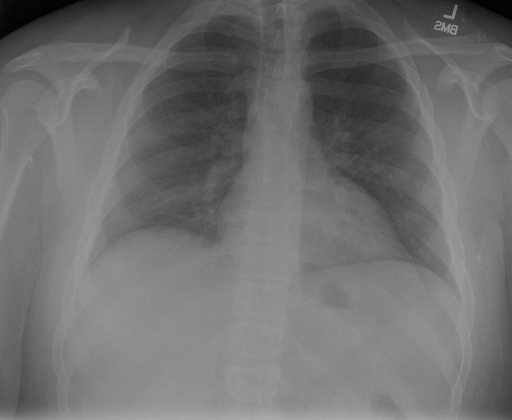

# 本文贡献  - 借助ChatGPT以及公开的数据集,我们构造了一个`X光影像-诊断报告`对的医学多模态数据集; # 数据集 - [MIMIC-CXR](https://physionet.org/content/mimic-cxr-jpg/2.0.0/)是一个公开可用的胸部X光片数据集,包括377,110张图像和227,827个相关报告。 - [OpenI](https://openi.nlm.nih.gov/faq#collection)是一个来自印第安纳大学医院的胸部X光片数据集,包括6,459张图像和3,955个报告。 在上述工作中,报告信息都为非结构化的,不利于科学研究。为了生成合理的医学报告,我们对两个数据集进行了预处理,并最终得到了可以用于训练的**英文报告**。除此之外,为了更好的支持中文社区发展,借助ChatGPT的能力,我们将英文报告进行了中文翻译,并最终形成了可用于训练的数据集。 |数据集|数量|下载链接| |:-|:-|:-| |MIMIC-CXR-zh|-|-| |OpenI-zh|6,423|[诊疗报告](./data/Xray/openi-zh.json) 、[X光影像](https://pan.baidu.com/s/13GBsDMKf6xBZBSHpoWH_EA?pwd=k9sh)| # 快速上手 1. 安装环境 ```bash # 安装依赖 pip install -r requirements.txt # 国内换源安装依赖 pip install -i https://mirrors.aliyun.com/pypi/simple/ -r requirements.txt ``` 此时默认会安装`deepspeed`库(支持`sat`库训练),此库对于模型推理并非必要,同时部分`Windows`环境安装此库时会遇到问题。 如果想绕过`deepspeed`安装,我们可以将命令改为: ```bash # 安装依赖 pip install -i https://mirrors.aliyun.com/pypi/simple/ -r requirements_wo_ds.txt # 安装SwissArmyTransformer pip install -i https://mirrors.aliyun.com/pypi/simple/ --no-deps "SwissArmyTransformer>=0.3.6" ``` 2. 模型推理 CLI推理: ```python python cli_demo.py --from_pretrained checkpoints/finetune-XrayGLM-05-25-01-04 --prompt_zh '详细描述这张胸部X光片的诊断结果' ``` 更多[参数](https://github.com/WangRongsheng/XrayGLM/blob/main/cli_demo.py#L16) # 效果展示 诊断: |X光影像|诊疗报告(医生)|XrayGLM| |:-|:-|:-| ||根据X射线图像,心脏大小正常,肺部看起来很清晰。已经排除了肺炎、积液、水肿、气胸、腺病、结节或肿块的存在。该发现表明一切正常。换句话说,总体印象是胸部正常。|X光片显示,心脏大小正常。肺部没有气胸或胸腔积液的证据。骨骼结构看起来没有任何异常。总的来说,X光片表明没有发现急性心肺疾病的迹象。| ||X光图片显示没有扭曲的区域、可疑的骨质不透明度或胸腺积液。心脏大小轻微增大,但非常稳定。此外,没有气胸的证据,肺野也正常。总体来说,X光片显示没有急性心脏异常,但要注意轻微的心脏扩大。|X光片显示,心脏大小正常。肺部和纵隔轮廓清晰,没有气胸或胸腔积液的证据。骨骼结构完整,没有任何急性异常。| ||心影形态在正常范围内。没有急性骨质异常。有可能出现没有明显的吸水或肺实质状况的线索。没有大面积积液或气胸。有可能怀疑其有误吸或肺实质问题。为了确诊和治疗,可能需要进行适当的影像学随访。|心脏大小正常,肺部和纵隔轮廓清晰。没有急性异常或活动受限的证据。没有任何明显的气胸、胸腔积液或肺不张的迹象。此外,也没有发现任何局灶性骨质异常或其他急性疾病。| 多轮对话: |X光影像|诊疗报告(医生)| |:-|:-| ||右侧主动脉突出观察到。心脏大小正常。胸部未发现明显的肺气肿、胸膜积液或可疑的肺部病变。报告指出已知右侧主动脉情况正常。| ```bash >> X光影像路径:./data/Xray/861_1.png >> 用户:这是一张什么图? >> XrayGLM:这张图片显示的是一张肺部检查的X光片。 >> 用户:请描述这张胸部X光片的诊断结果 >> XrayGLM:心脏大小正常,肺部清晰。没有急性心肺疾病的证据。 >> 用户:是否存在肺气肿? >> XrayGLM:没有肺气肿。心脏大小正常,肺部清晰。没有发现急性心肺疾病的证据。 >> 用户:平时饮食该注意什么? >> XrayGLM:饮食应该健康,均衡。建议增加蛋白质的摄入量,因为蛋白质有助于维持肌肉和骨骼的健康。多食用蔬菜、水果、全谷物以及健康的脂肪来源如橄榄油、鱼类等可以帮助获得足够的维生素和矿物质。此外,避免过度饮酒或吸烟,这些习惯可能会对心脏健康产生负面影响。 ``` # 项目致谢 1. [VisualGLM-6B](https://github.com/THUDM/VisualGLM-6B)为我们提供了基础的代码参考和实现; 2. [MiniGPT-4](https://github.com/Vision-CAIR/MiniGPT-4)为我们这个项目提供了研发思路; 3. ChatGPT生成了高质量的中文版X光检查报告以支持XrayGLM训练; 4. [gpt_academic](https://github.com/binary-husky/gpt_academic)为文档翻译提供了多线程加速; 5. [MedCLIP](https://github.com/RyanWangZf/MedCLIP) 、[BLIP2](https://huggingface.co/docs/transformers/main/model_doc/blip-2) 、[XrayGPT](https://github.com/mbzuai-oryx/XrayGPT) 等工作也有重大的参考意义;  这项工作由[澳门理工大学应用科学学院](https://www.mpu.edu.mo/esca/zh/index.php)硕士生[王荣胜](https://github.com/WangRongsheng) 、[段耀菲](https://github.com/IsBaSO4) 、[李俊蓉](https://github.com/lijunrong0815)完成,指导老师为檀韬副教授、[彭祥佑](http://www.patrickpang.net/)老师。 *特别鸣谢:[USTC-PhD Yongle Luo](https://github.com/kaixindelele) 提供了有3000美金的OpenAI账号,帮助我们完成大量的X光报告翻译工作 # 免责声明 本项目相关资源仅供学术研究之用,严禁用于商业用途。使用涉及第三方代码的部分时,请严格遵循相应的开源协议。模型生成的内容受模型计算、随机性和量化精度损失等因素影响,本项目无法对其准确性作出保证。即使本项目模型输出符合医学事实,也不能被用作实际医学诊断的依据。对于模型输出的任何内容,本项目不承担任何法律责任,亦不对因使用相关资源和输出结果而可能产生的任何损失承担责任。 # 项目引用 如果你使用了本项目的模型,数据或者代码,请声明引用: ```bash @misc{wang2023XrayGLM, title={XrayGLM: The first Chinese Medical Multimodal Model that Chest Radiographs Summarization}, author={Rongsheng Wang, Yaofei Duan, Junrong Li, Patrick Pang and Tao Tan}, year={2023}, publisher = {GitHub}, journal = {GitHub repository}, howpublished = {\url{https://github.com/WangRongsheng/XrayGLM}}, } ``` # 使用许可 此存储库遵循[CC BY-NC-SA](https://creativecommons.org/licenses/by-nc-sa/4.0/) ,请参阅许可条款。